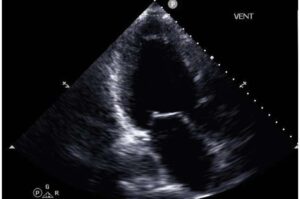

Applying artificial intelligence techniques to cardiac ultrasound data may make it easier to identify patients with advanced heart failure, a new study has found. The study—led by investigators at Weill Cornell Medicine, Cornell Tech, Cornell Ann S. Bowers College of Computing and Information Science, Columbia University Vagelos College of Physicians and Surgeons and NewYork-Presbyterian—offers the prospect of better care for many thousands of patients who may be overlooked due to the difficulty of diagnosing their condition.